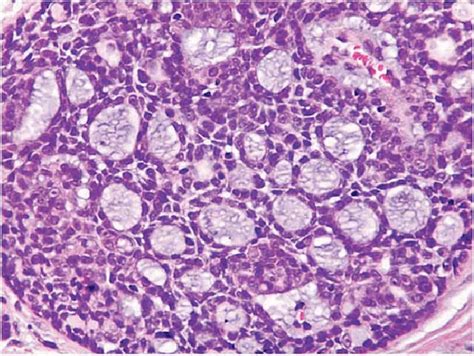

Now, let’s get to the heart of the matter: the tubular pattern of adenoid cystic carcinoma . When pathologists look at a biopsy sample under a microscope, they’re essentially trying to identify distinct structures and cell arrangements that help them diagnose the specific type of cancer. The tubular pattern in ACC is characterized by the formation of small, tube-like structures, or ducts , made up of cancer cells. Imagine tiny, imperfect cylinders or tubules. These tubules are typically lined by two distinct layers of cells: an inner layer of luminal cells (the cells forming the lining of the tube) and an outer layer of myoepithelial cells . Myoepithelial cells are special cells that normally surround the ducts of glands and help with secretion. In the tubular pattern, these cells are often seen proliferating and forming these characteristic small, round or oval tubules. These structures are usually quite uniform in size and shape, and they are often separated by a stromal background, which is the supporting connective tissue. The key here is the presence of these well-defined, small, duct-like formations . It’s a bit like looking at a microscopic blueprint of a glandular structure that’s gone awry. The cells themselves are usually described as having hyperchromatic (darkly stained) nuclei and scant cytoplasm. The formation of these tubules is a defining feature, distinguishing it from other patterns like the cribriform pattern (which looks like sieves or Swiss cheese) or the solid pattern (which is just sheets of cells). The amount of each pattern can vary within a single tumor, and often a tumor will exhibit a mixture of patterns. However, the presence of a significant tubular component is what defines this specific subtype. This organized, yet malignant, arrangement is what pathologists meticulously identify to arrive at an accurate diagnosis, which is the first crucial step in planning effective treatment. This precise identification helps guide the clinical team in understanding the potential behavior of the tumor and in making informed decisions regarding therapy. The elegance of this microscopic view lies in its ability to reveal the intricate nature of the disease at its most fundamental level, allowing for targeted interventions.

So, what exactly are the tell-tale signs that a pathologist looks for when they suspect the tubular pattern of adenoid cystic carcinoma ? It’s like being a detective, searching for specific clues under the microscope. The primary characteristic, as we’ve discussed, is the presence of small, uniform, duct-like structures or tubules . These tubules are typically lined by two cell layers: an inner layer of epithelial cells and an outer layer of myoepithelial cells. The key here is that these structures are well-formed and distinct , setting them apart from haphazard cell arrangements. The tubules are often round or oval and vary in size but are generally small. The cells forming these tubules are usually described as having basaloid features , meaning they have dark, round to oval nuclei with scant cytoplasm. Another critical feature that often accompanies the tubular pattern, and is a hallmark of ACC in general, is perineural invasion . This is when the cancer cells are seen growing along or within the nerves. This is a very important prognostic indicator and is meticulously searched for by pathologists. You’ll see the tumor cells infiltrating the spaces around nerve fibers. The presence of a hyalinized or mucoid stroma is also common. This refers to the supportive connective tissue surrounding the tubules, which can appear glassy (hyalinized) or contain mucus-like material. This background helps to separate the neoplastic tubules. Unlike the cribriform pattern, where you see large, sievelike spaces formed by the tumor cells, the tubular pattern features individual, small lumens within the tubules. The solid pattern, conversely, lacks these distinct glandular or tubular formations and consists of sheets or nests of tumor cells. Often, ACC tumors are mixed , meaning they can show a combination of tubular, cribriform, and solid patterns. However, if a significant portion of the tumor displays these well-defined tubular structures, it will be classified as having a tubular pattern. The pathologist will assess the percentage of each pattern present, as this can sometimes influence prognosis. So, in essence, it’s the combination of small, organized, duct-like structures lined by specific cell types, often accompanied by perineural invasion and a characteristic stromal background, that paints the picture of the tubular pattern of ACC. This detailed microscopic evaluation is absolutely vital for accurate diagnosis and treatment planning.